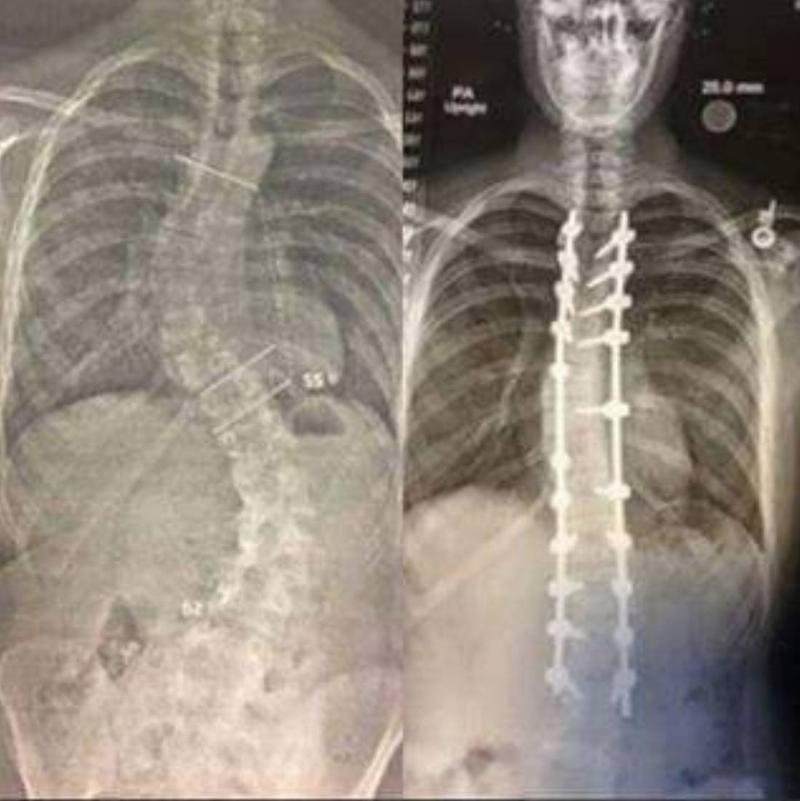

These Are Pre And Post-Op X-Rays

x-rays show before (crooked spine) and after (spine straighter with rods)

This person went in for surgery to help correct their spine, which was crooked from scoliosis.

The surgery took 14 hours, but the right side shows how much the surgery helped straighten their spine.